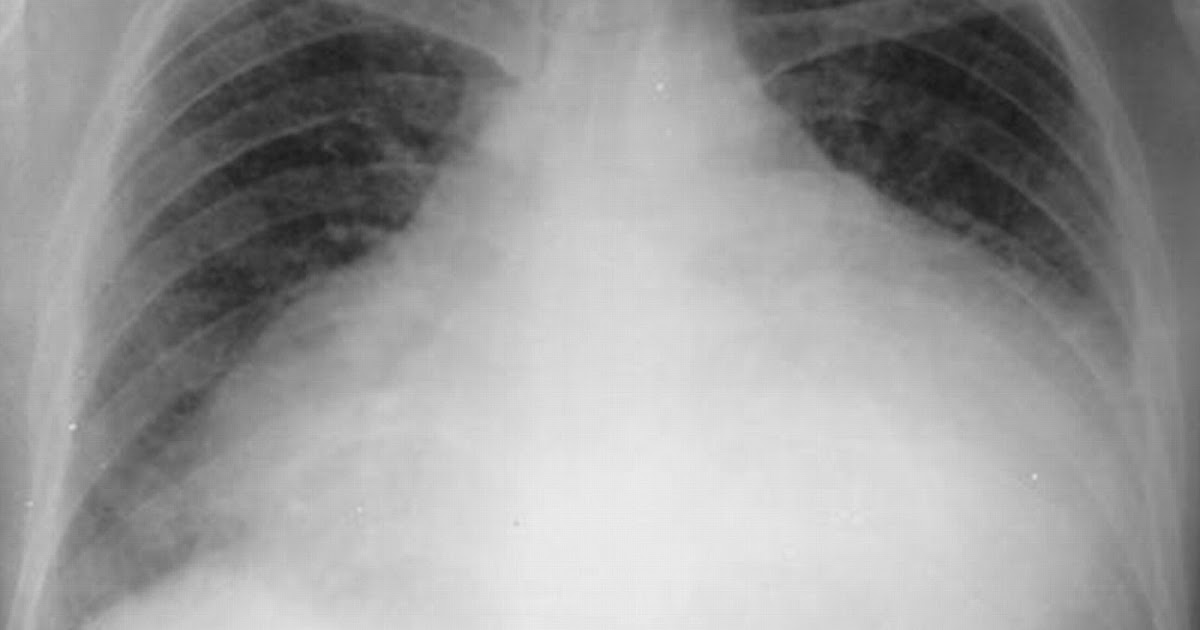

Guide To The Causes Of Acute Respiratory FailureThe primary purpose of the respiratory system is to exchange gases when individuals breathe. The lungs are the most important part of this system. Failure occurs…March 7, 2019